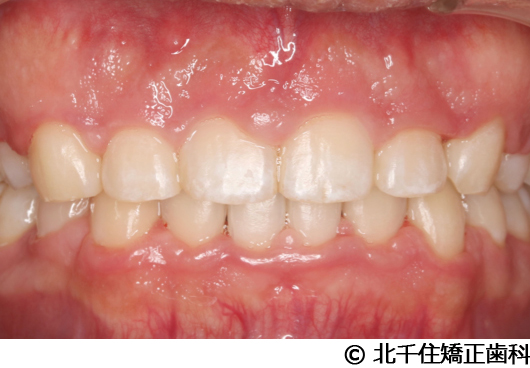

【症例2】上顎前突症

- 治療後

主訴:出っ歯、口元の突出、横顔をきれいにしたい

骨格性の上顎前突、上下顎第一小臼歯4本及び上顎第二大臼歯を抜歯して矯正用アンカースクリューを併用してワイヤー矯正治療(セラミックブラケット)。

治療結果

骨格性上顎前突に対し、抜歯および矯正用アンカースクリューを併用した矯正治療により歯列および咬合関係の調整を行った症例である。治療後は保定装置を使用し、歯列および咬合の安定維持を目的として定期的な経過観察を行っている。

※治療結果は個人差があります。

治療を行う上での注意点(リスク・副作用)

歯磨き不良に伴うカリエスや歯周病、顎関節症、歯根吸収など。